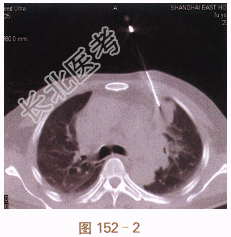

二、影像学资料

常规CT扫描定位(见图152-1),注射器针头扫描确认位置与进针角度。穿刺活检针达病灶边缘,再次扫描确认位置与角度(见图152-2)。行切割活检,取出病理组织(见图152-3)。